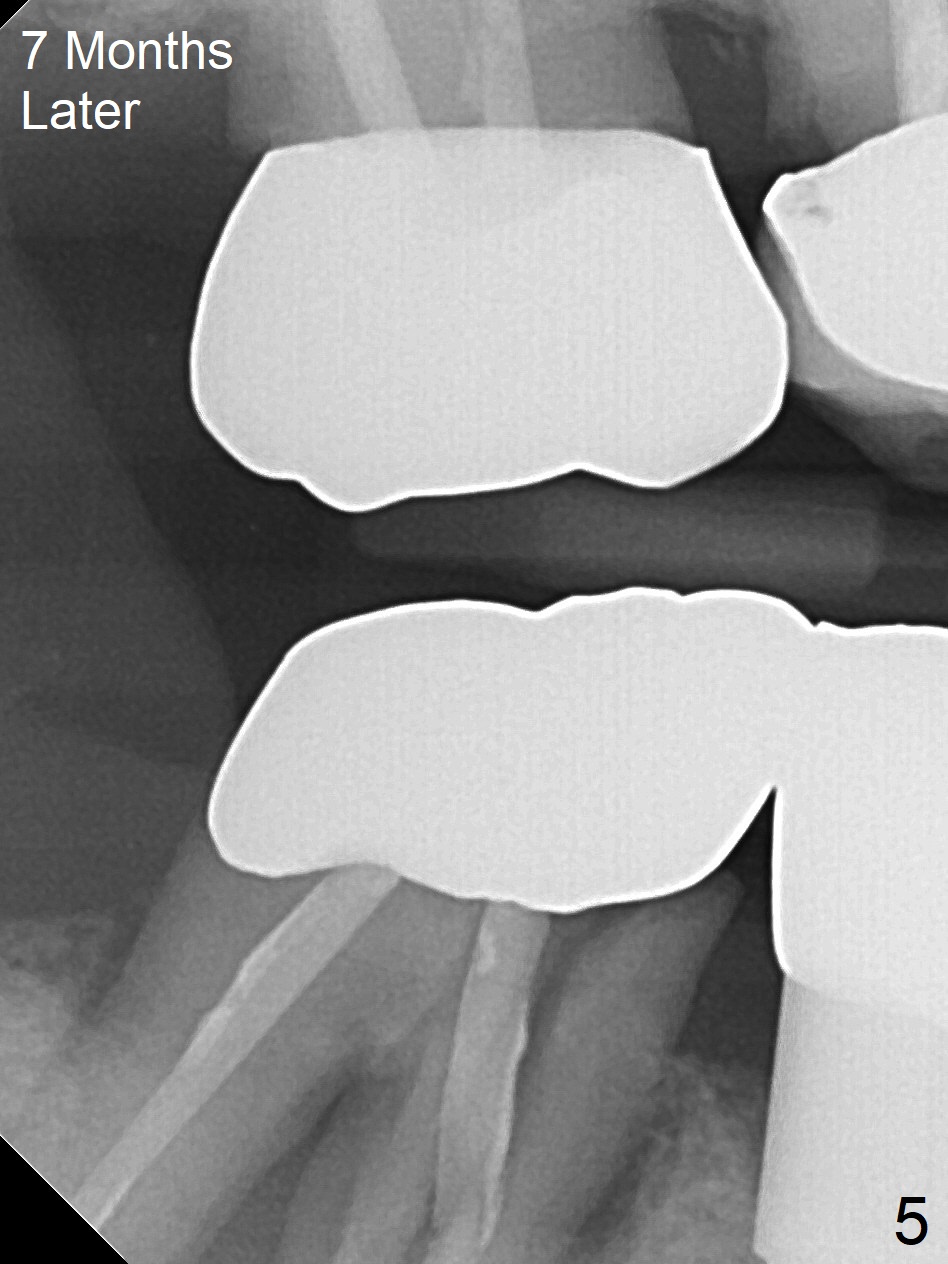

A 87-year-old man was asymptomatic with the tooth #31 eight months earlier (Fig.1), as compared to now (Fig.2). After extraction, osteotomy will be initiated in the septum (where there is more bone height) using IS 6 mm stopper (Fig.3 red line), followed by PA. If PA does not show the Inferior Alveolar Canal (Fig.1 red dashed line), take panoramic X-ray. A 5.5x13 mm implant will be placed (7 mm may not be covered by the native bone). The mesial root vertical root fracture is more obvious 7 months later (Fig.4,5).